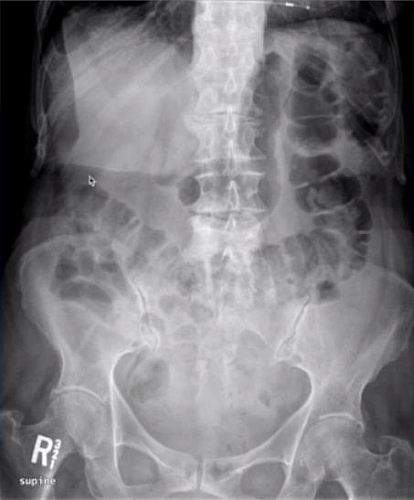

All students are invited to prepare a short review on standard plain abdominal radiograph discussing briefly its common indications, contraindications and diagnostic value.